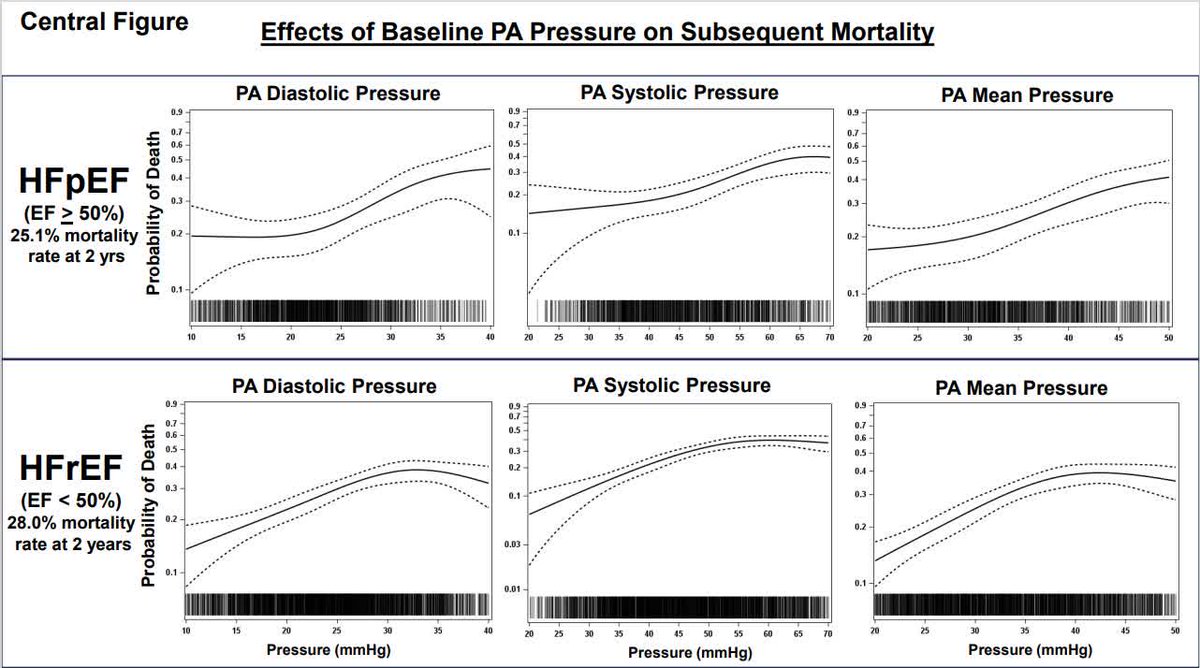

Relationship Between Remote, Ambulatory Pulmonary Artery Pressures, and All-Cause Mortality in Patients With Chronic Heart Failure Akshay Desai anique ducharme Christiane E. Angermann DocMRM-Heart Maria Rosa Costanzo #AHAJournals ahajrnls.org/4lCfZ5n